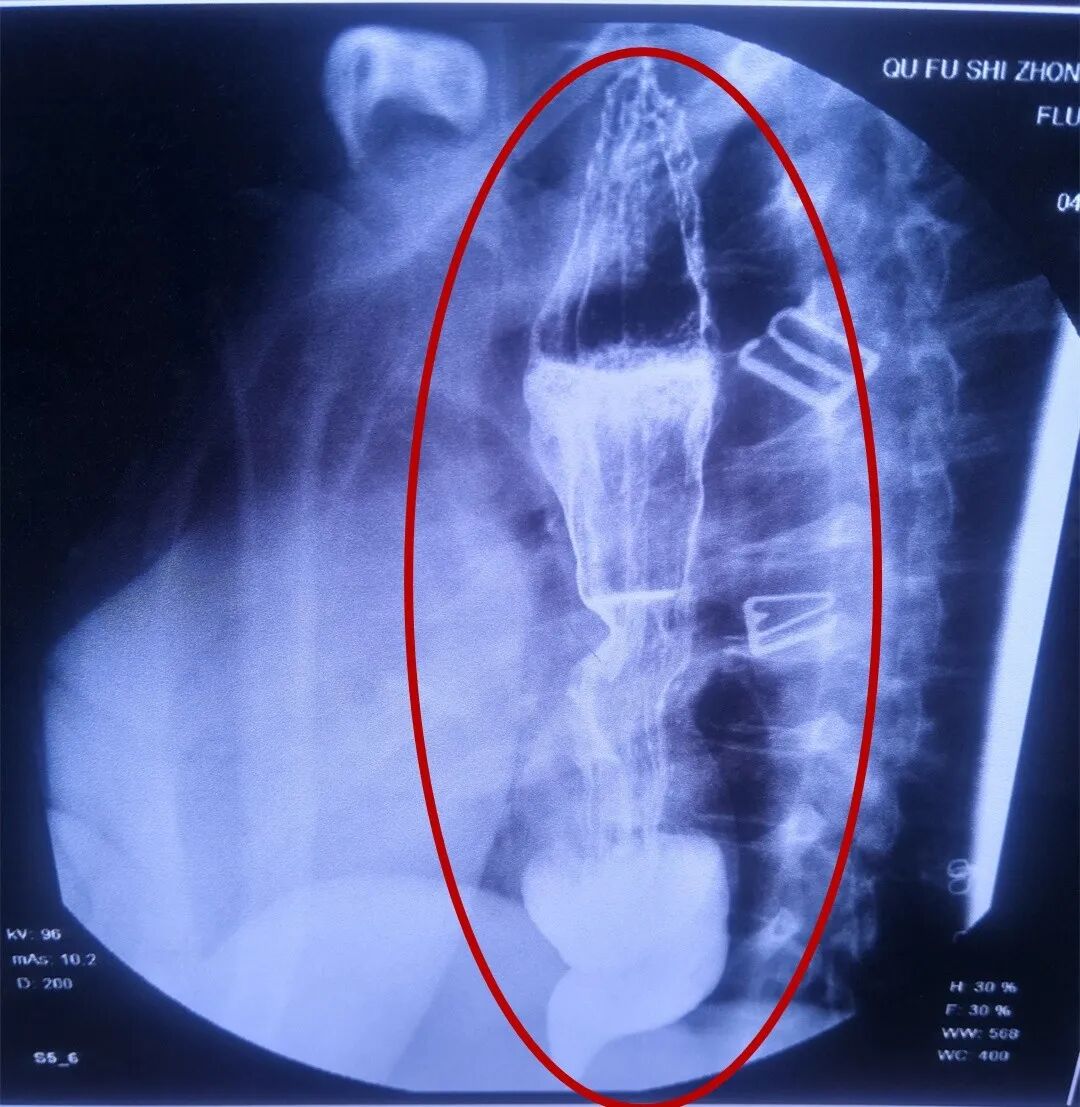

术后食管修复回缩

近日复查上消化道钡餐及CT示恢复良好,食管通畅,已明显回缩,开放良好,胃肠排空好。李大姐现已正常生活。